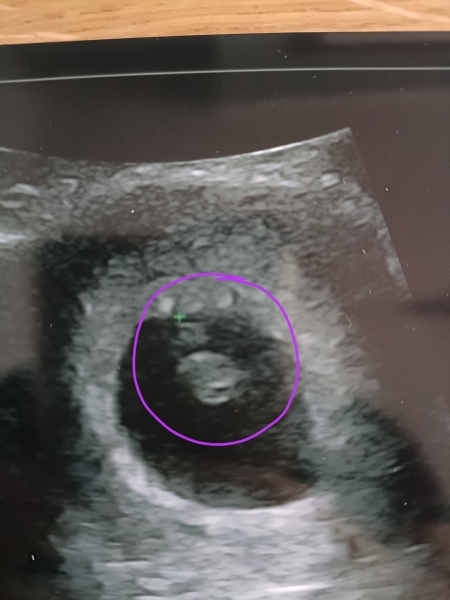

Baby is snug in my tummy 🥰

Been for a private scan this morning ... 🥹 We have a healthy heart beat , 165 BPM , measuring 1.18cm , 7 weeks and 3 days. Due date 4th Feb 2025 ✨ xx